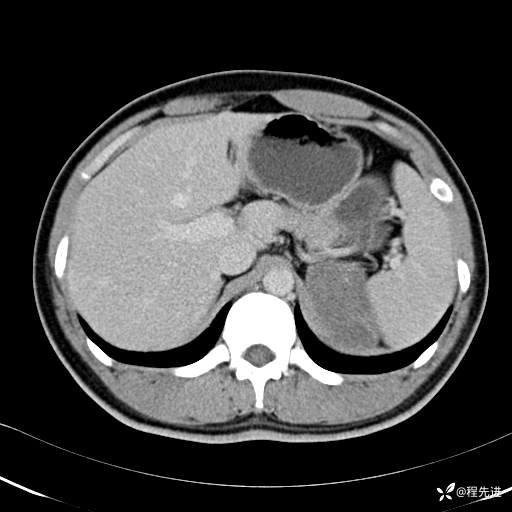

【腹盆】特别精彩病例|体检发现的左侧腹膜后占位期待您的精彩解读

患者年龄:25岁

简要病史:体检发现

CT平扫:(CT值:平扫,27HU,动脉期,27HU,门静脉期,31HU,平衡期,32HU)

CT增强:

动脉期: